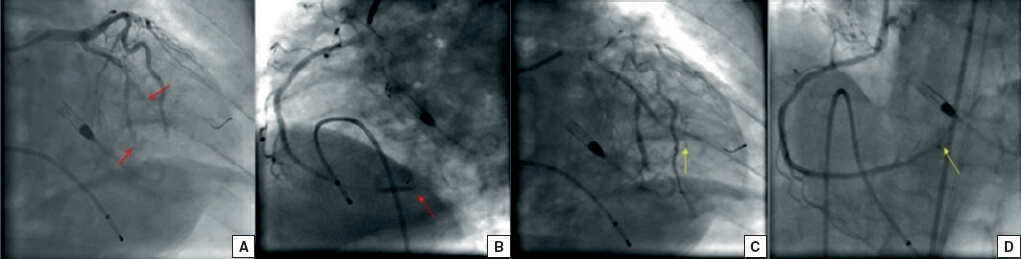

A su llegada al laboratorio de hemodinámica el paciente persistía en situación de shock cardiogénico y además presentaba bloqueo auriculoventricular completo. Se implantó de forma emergente por vía venosa femoral derecha un marcapasos temporal y la por arteria femoral izquierda se implantó un dispositivo Impella CP (AbioMed, Danvers, Massachusetts, Estados Unidos). Por acceso femoral derecho se realizó la coronariografía, que mostró oclusión aguda de aspecto embólico en la circunfleja media y la coronaria derecha distal (figura 1A, B). Se realizó tromboaspiración en ambas arterias y se obtuvo abundante material trombótico. Se llevó a cabo una angioplastia simple en la coronaria derecha distal, con un restablecimiento subóptimo del flujo epicárdico (Thrombolysis in Myocardial Infarction ≤ 2) (figura 1C, D). Tras el intervencionismo se realizó ecocardiografía transtorácica que mostró la presencia de una masa intracavitaria adherida al techo de la aurícula izquierda con extensión al ventrículo izquierdo (figura 2). Ante estas imágenes y la inestabilidad hemodinámica persistente a pesar de los fármacos vasoactivos a dosis máximas y el soporte circulatorio percutáneo, se contactó con el equipo de cirugía cardiaca y se decidió implantar un oxigenador extracorpóreo de membrana de forma percutánea y retirar el Impella CP.

Figura 1. A: las flechas muestran embolización de la circunfleja distal. B: la flecha muestra embolización de la coronaria derecha distal. C-D: las flechas muestran el resultado tras el intervencionismo.